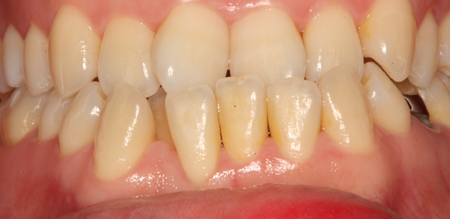

치주치료 전후사진

치주염 단계별 증상

치은염 (초기~중기)

치아 주위의 잇몸이 붉게 부어 있으며, 칫솔질 등을 할 때 피가 남.

스케일링 주기의 조절이 필요할 수 있으며, 올바른 칫솔질을 시행하여야 함.

치주염 (중기~말기)

주기적으로 잇몸이 붓고 피가 나며, 욱씬하거나 우리한 통증이 나타남.

치주치료 및 정도에 따라 치주수술(잇몸수술)이 필요함. 향후 관리 정도에 따라 3~6개월 간격으로 내원하여 유지치료를 시행하여야 함.

치주염 (말기)

잇몸이 항상 부어 있으며, 이가

흔들리는 정도가 점점 심해짐.

치주치료가 필요하며, 정도에 따라 치아를 발치하여야 할 수 있음.